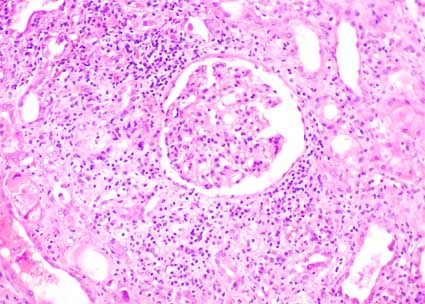

Mujer de 27 años de edad, trasplantada de riñón

cadavérico debido a falla renal terminal de causa desconocida.

La evolución en las primeras semanas del trasplante fue buena,

sin complicaciones. El tratamiento inmunosupresor consistió en

ciclosporina, micofenolato mofetil y prednisona. Tres meses después

del trasplante presenta elevación de la creatinina sérica:

3,0 mg/dL. No tenía episodios previos de rechazo. Proteinuria:

200 mg/dL; no hematuria. No presentaba síntomas sistémicos.

La ecografía renal no mostró alteraciones;

flujo arterial y venoso normales.

Con un diagnóstico presuntivo de rechazo agudo

se hace biopsia renal:

Figura 1.

H&E, X200.